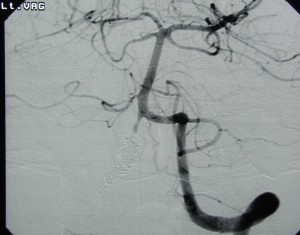

<入院時の頭部CT;くも膜下出血を認める>

<右解離性椎骨動脈瘤:矢印>